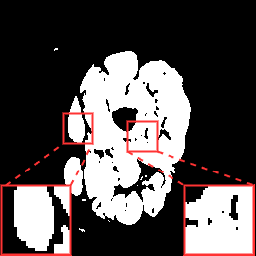

(a) Image

(b) GT

(c) Baseline

(d) Our method

(e) ResU-Net

(f) AttU-Net

(g) MC-Net

(h) Fully U

Table 1 lists the quantitative results (evaluated on the testing data) including state-of-the-art approaches for the following methods: U-Net (Baseline) [5], ResU-Net [7], AttentionU-Net [6, 22], MC-Net [15], a fully supervised U-Net, and our proposed method. Qualitative results are shown in Fig. 3. When only labeled 2D samples were available for training, the proposed method outperformed all the compared methods with an improvement of the and metrics of and when compared to the baseline. Furthermore, our method proposal with a low number of samples gave results comparable to those of a fully supervised U-Net trained with labeled samples.